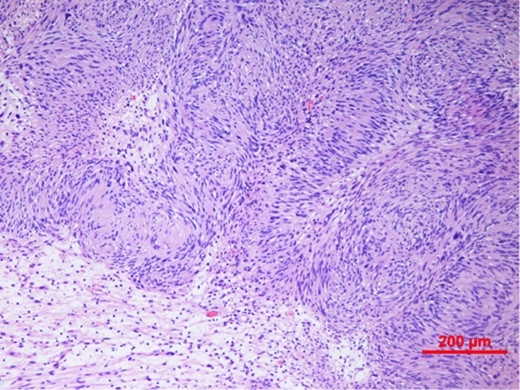

Our patient underwent an excisional biopsy without a preoperative needle biopsy. A 1.2 × 1.2 × 0.8 cm smooth well-encapsulated nodule was removed in entirety from the breast parenchyma. On bisection, the cut section displayed a pale pink smooth homogeneous appearance. Microscopic evaluation showed an encapsulated spindle cell tumour with prominent nuclear palisading and features typical of a schwannoma (Fig. 3). There was also strong and diffuse positive staining of S-100, favouring the diagnosis of schwannoma (Fig. 4). There was no evidence of malignancy in the specimen.

Spindle cell tumour with palisaded arrangement of nuclei, typical of schwannoma. Cellular (Antoni A) areas alternate with looser myxoid (Antoni B) areas.

Macroscopically, breast schwannomas are described as white, grey, tan or pink well-encapsulated masses. Microscopically, they are spindle cell tumours with Antoni A patterns (hypercellular areas with palisading nuclei surrounding pink areas called Verocay bodies) and Antoni B patterns (hypocelluar regions with looser stroma and myxoid change) Schwannomas almost always stain positive for S100 protein. A cytologic diagnosis via fine needle aspiration may be possible if clusters of spindle-shaped cells arranged in a palisading fashion and lacking epithelial elements are seen [3].